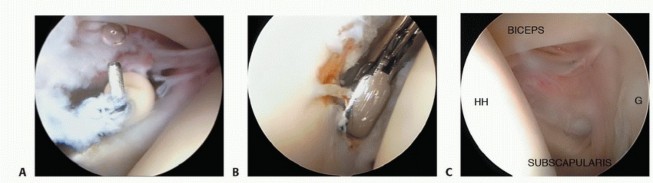

1. ## Anterior Capsular Release

Resection of contracted and thickened capsule can be done with a radiofrequency device, shaver, or arthroscopic punch.

We prefer to use a hook-tipped radiofrequency device to avoid bleeding, resect in a controlled fashion, and benefit from the feedback of electrical stimulation to nearby muscles and nerves.

An arthroscopic punch can be used once a leading edge in the capsule has been established (

TECH FIG 2A,B

).

In adhesive capsulitis, the capsule is often up to 1 cm thick compared with the normal 2 mm. We resect the anterior capsule systematically.

The rotator interval capsule is noted between the biceps superiorly and the intra-articular subscapularis inferiorly. This comprises the superior glenohumeral and coracohumeral ligaments (

TECH FIG 2C

We begin by cutting (ablating) the capsular tissue immediately inferior to the biceps tendon (

TECH FIG 2D

TECH FIG 2

• Capsule can be resected by (

A

) a radiofrequency device or (

B

) an arthroscopic punch.

C.

The rotator interval is the portion of the capsule between the supraspinatus and subscapularis. Arthroscopically, it is seen bordered by the biceps, subscapularis, humeral head (

HH

), and glenoid (

G

D.

The capsule in the rotator interval is incised lateral and parallel to the glenoid starting inferior to the biceps.

E.

The capsule is incised from just inferior to the biceps up to the leading edge of the subscapularis (

subscap

) tendon.

(continued)

The capsular tissue is released inferiorly until the superior border of the subscapularis is identified, thus releasing the rotator interval and its contents (

TECH FIG 2E

A switching stick can then be used to bluntly dissect the capsule from the deep surface of the subscapularis to create a defined interval. This capsule represents the middle glenohumeral ligament (

TECH FIG 2F

The capsule overlying the subscapularis is then divided to the 6 o’clock position (

TECH FIG 2G

Gentle external rotation can place the capsule under additional tension and facilitate its resection.

The axillary nerve is not at risk as long as the subscapularis muscle is seen (see

FIG 1C